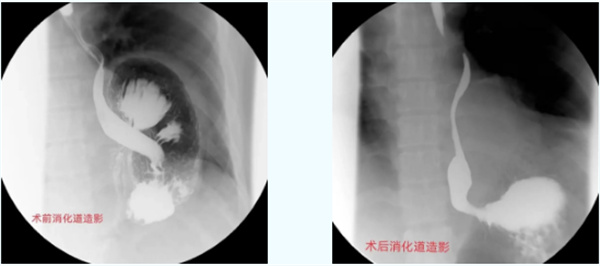

1周前,一位20多岁的年轻小伙来到市人民医院胸心外科肿瘤外科门诊就诊。虽然患者年轻,但是“反酸烧心”不适感已有1年多,经过反复多次的内科治疗,症状时轻时重,均没有得到彻底的缓解。患者打听到市人民医院胸心外科肿瘤外科可以经过手术治疗解除“顽疾”,于是便火急火燎地前来就诊,希望能够解除病痛。经检查明确为“食管裂孔疝”,而且患者疝囊较大,导致胃翻转,出现了难以根治的“反酸烧心”不适。患者入院完善术前准备后,给予“全麻下腔镜下食管裂孔疝修补术+Nissen术”,因为是微创手术,术后患者痛苦小、恢复快,短短几天患者反酸烧心不适已完全消失,感激的对科主任陈瑜说道:困扰他多年的老顽疾,一下子没了,感觉浑身都轻松了,特别感谢胸心外科肿瘤外科团队的精心治疗。

食管裂孔疝、反流性食管炎,一种常见的消化系统疾病;均可引起胃、十二指肠内容物反流入食管引起的食管炎症性病变,导致食管黏膜的损伤,出现反酸烧心、上腹胀痛、胸痛、嗳气等症状,长期会引起贫血;特别是食管裂孔疝,腹腔脏器通过扩大的食管裂孔进入胸腔,压迫肺组织、心脏等重要脏器,产生胸闷气短等严重不适,甚至可能会因为疝内容物的嵌顿,引起消化道穿孔、缺血坏死,出现呕血、黑便、贫血等症状,严重者可危及生命。很多患者朋友出现类似症状后,都选择内科保守治疗,大部分患者通过内科治疗可缓解症状,但也有部分患者内科治疗效果较差,症状持续存在,严重影响生活质量,应明确有无食管裂孔疝;或者需要行食管胃抗反流折叠术,达到更好的治疗效果。目前基本通过微创腔镜完成此类手术,显示更清晰,操作更细致,具有微创、痛苦小、术后恢复好、住院时间短等优点,不但极大的缓解了患者痛苦,同时减轻患者因住院时间长导致的经济负担,被患者普遍接受。